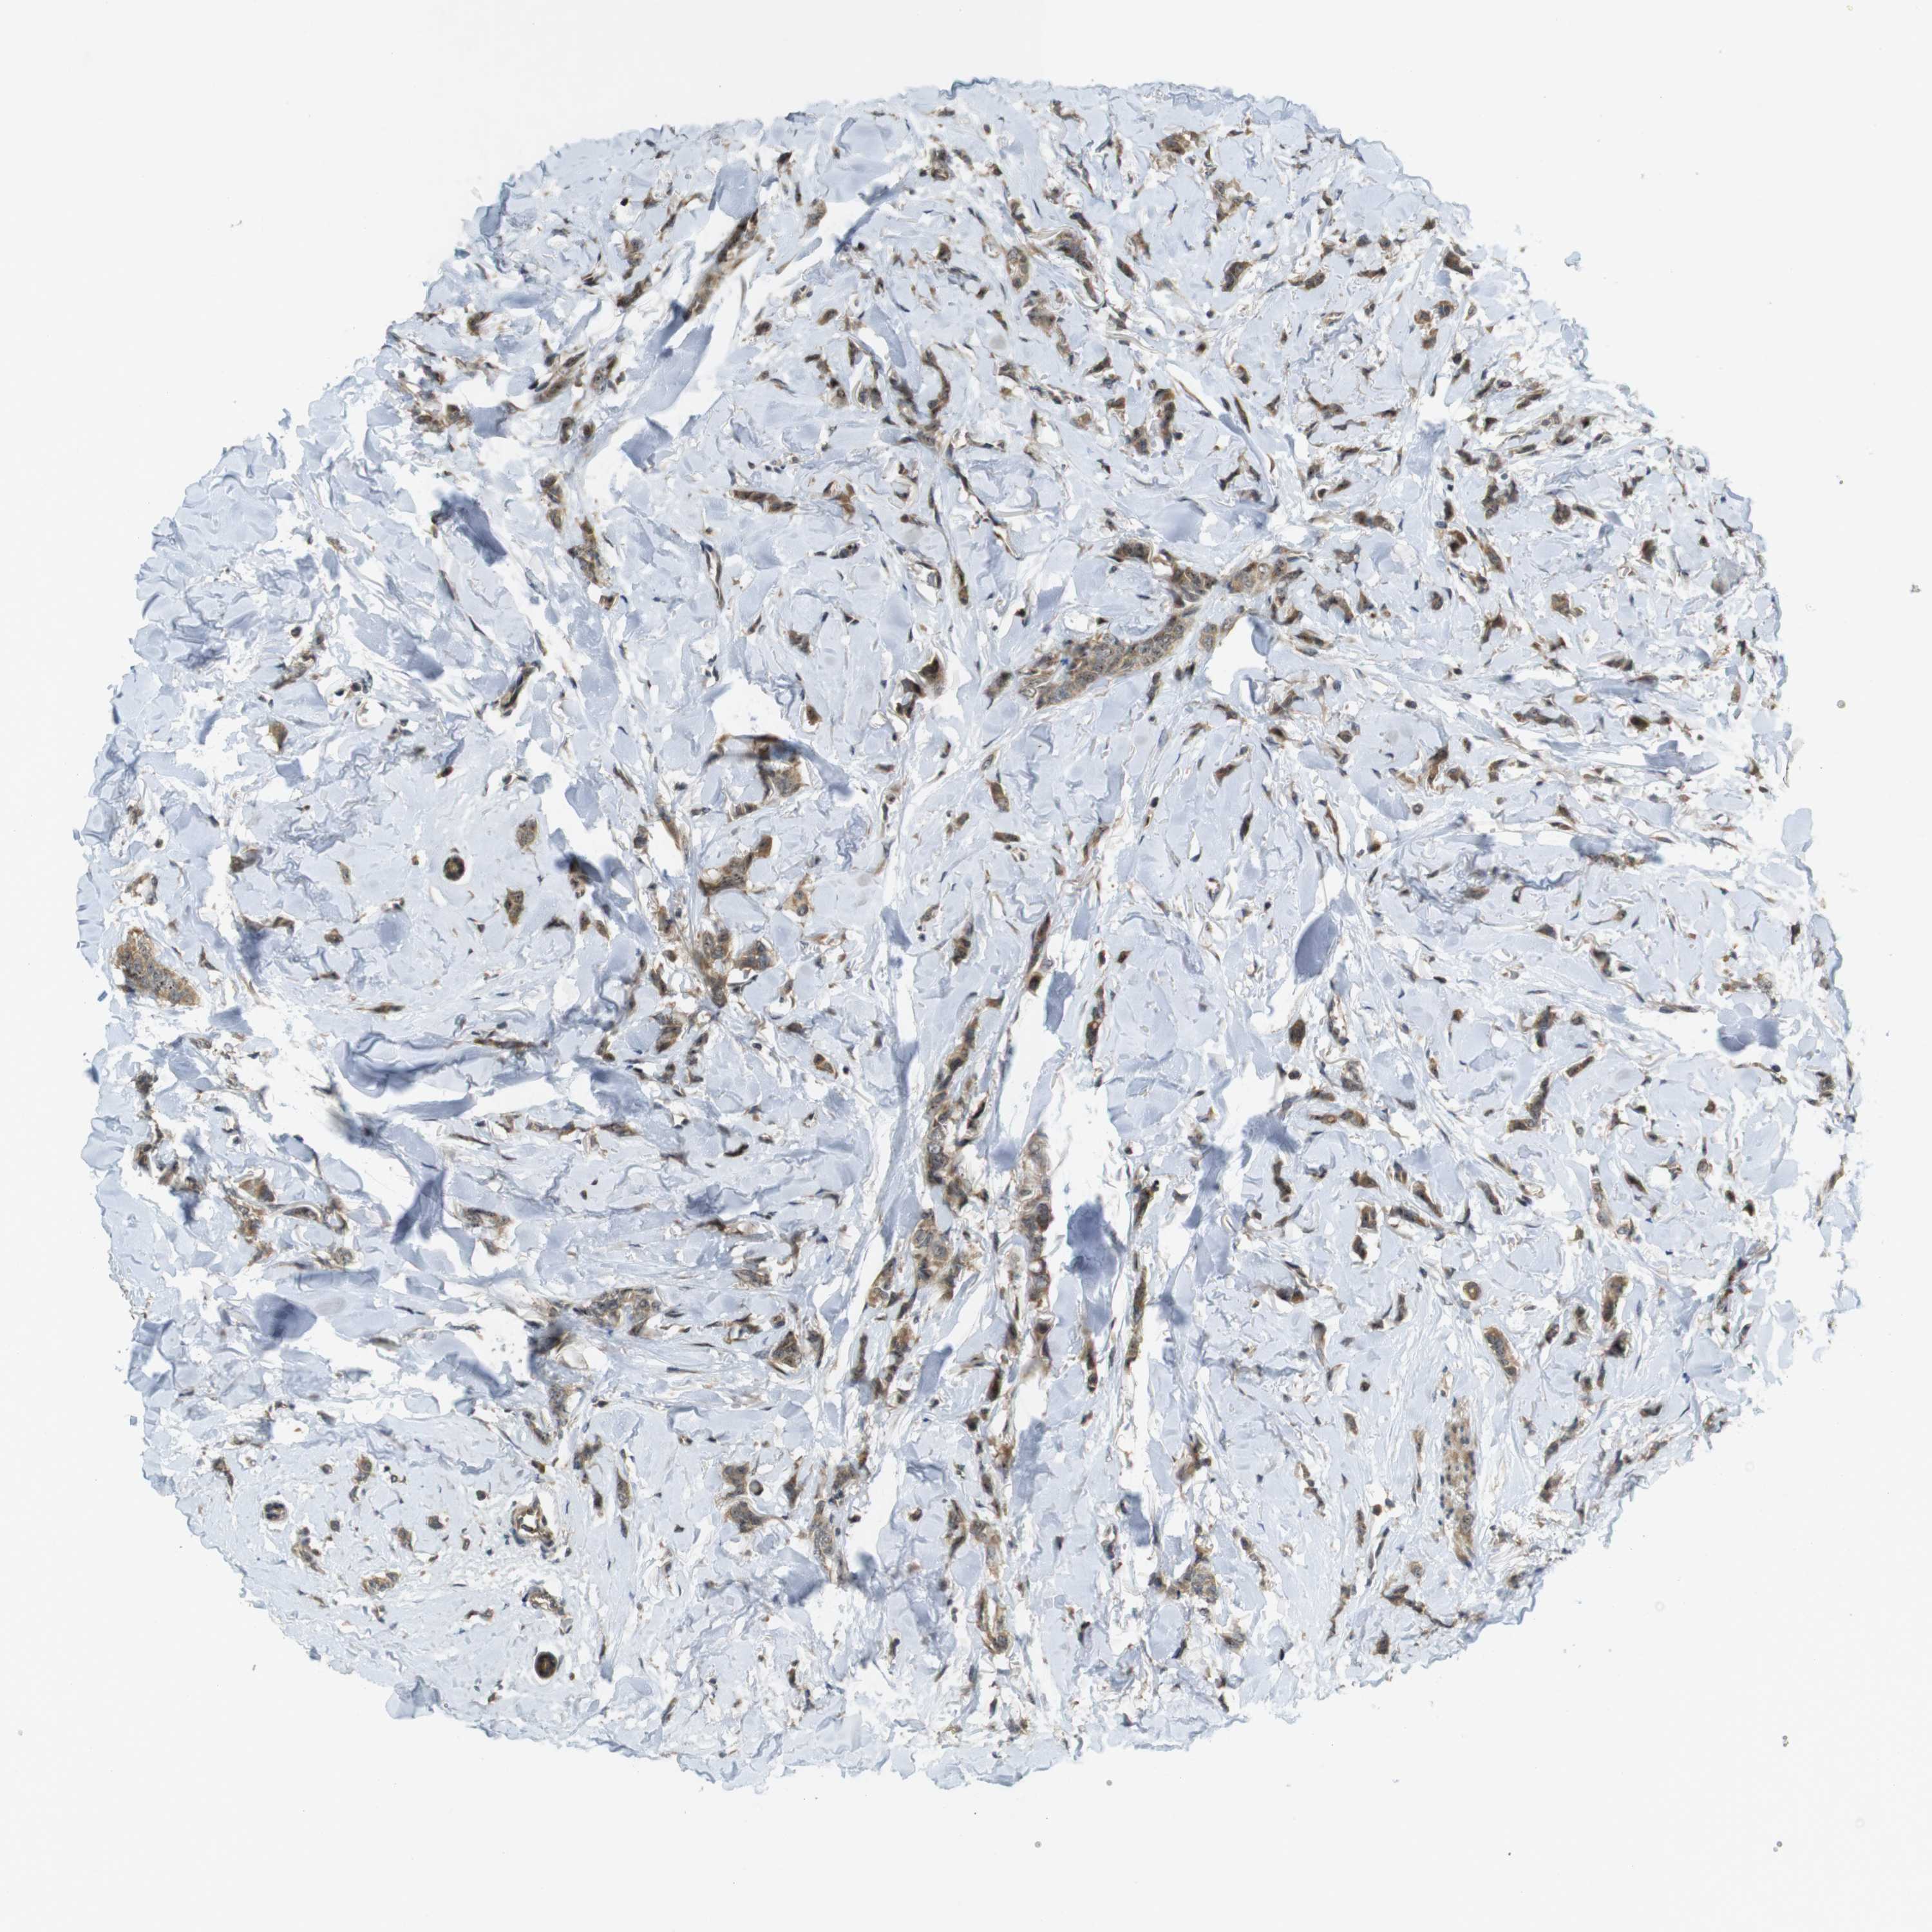

BRCA TCGA BRCA VALIDATION PROTEIN EXPRESSION

ANTIBODIES

AND

VALIDATION